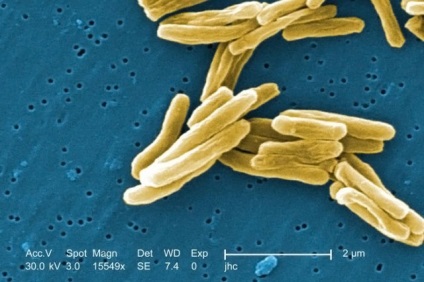

- Fertőző-allergiás módon. Jellemző Mycobacterium tuberculosis. Ez annak a ténynek köszönhető, hogy ha belép az emberi test mycobacteria túlérzékenységet történik, azaz a fejlesztési túlérzékenység rá.

Micrograph: Mycobacterium tuberculosis.

Ezért bármilyen új előfordulása bakteriális ágens indukálhatja hatékony válasz formájában tüdőgyulladás héj hordozó általában váladékos karakter.